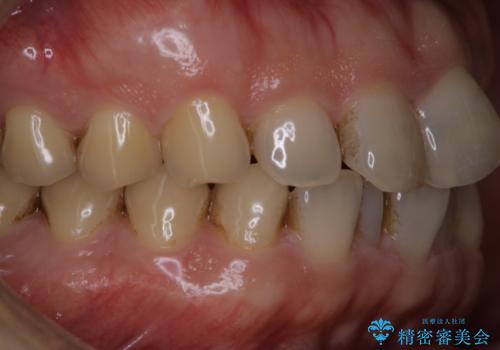

細かいステインをPMTCでOFF

- 歯ブラシをしてもとれないステインが気になるとのことで来院されました。PMTC60分コースを行いました。

PMTCは、歯に付着した汚れを除去していくため、着色が気になる場合にも行うことができます。ご自身でのセルフケアだけで着色を落とそうとすると、逆に歯を傷つけてしまったり、精密に汚れを除去できないこともあります。また、日常生活で着色しやすい飲食物を避けたりすることはストレスに感じてしまったり、あまり現実的ではありません。

毎日丁寧に歯磨きをしていても、日常生活での飲食物などにより着色してしまうことはあります。PMTCでは、歯の表面の凸凹にミネラルを補給して、ツルツルの表面に仕上げます